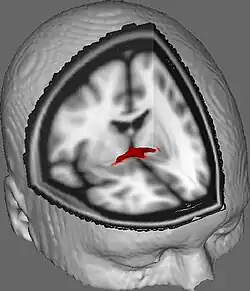

La commissure antérieure, appelée également la commissure blanche antérieure ou encore la précommissure (en latin : commissura anterior), est une commissure inter-hémisphérique qui croise transversalement la paroi antérieure du troisième ventricule[1]. C'est un faisceau nerveux de substance blanche (un paquet d'axones) qui relie les deux lobes temporaux des hémisphères cérébraux à travers la ligne médiane, et il se trouve en avant des colonnes du fornix (les piliers antérieurs trigone du cerveau). Chez la plupart des mammifères existants, la grande majorité des fibres reliant les deux hémisphères traversent le corps calleux, qui est plus de 10 fois plus grand que la commissure antérieure, et d'autres voies de communication passent par la commissure de l'hippocampe ou indirectement, via des connexions sous-corticales. Néanmoins, la commissure antérieure est une voie importante qui peut être distinguée clairement dans les cerveaux de tous les mammifères.

Dans une section sagittale, la commissure antérieure est de forme ovale, ayant un long axe vertical qui mesure environ 5mm.

Le fonctionnement de la commissure antérieure demeure pas encore élucidé complètement. Les chercheurs l'ont impliqué dans plusieurs fonctions allant de la perception des couleurs à l'attention. Une de ces études a soutenu la perception des couleurs dans l'agénésie du corps calleux (Ceux nés sans corps calleux; Barr & Corballis, 2002)[6]. D'autres études se sont appuyées sur cela pour impliquer que la commissure antérieure peut être une voie compensatoire chez les personnes sans corps calleux, présentant des techniques d'imagerie diffusion pour mieux élucider la commissure antérieure et comment elle pourrait être impliquée dans diverses fonctions (Winter & Franz, 2014).